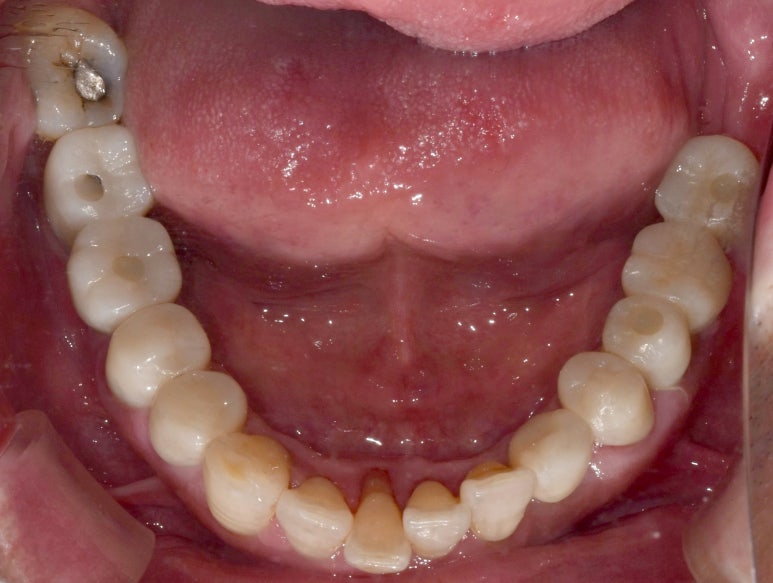

임플란트건강보험 시술 전후 모습

(전) 2021-11-05 (후) 2022-08-26

실제 사진을 보니 확실히 얼마나 달라졌는지 느낌이 오시죠? ^^

치아를 상실했던 부분이 완전히 채워진 것은 물론, 기존에 약했던 치아들도 모두 튼튼하게 교체해

음식을 씹을 때 전혀 지장이 없으시게끔 치료가 완료되었습니다.

환자분께서도 씹는 즐거움을 다시 느끼게 되셨다며 너무 좋아하셨던 모습이 눈에 선합니다 ^^